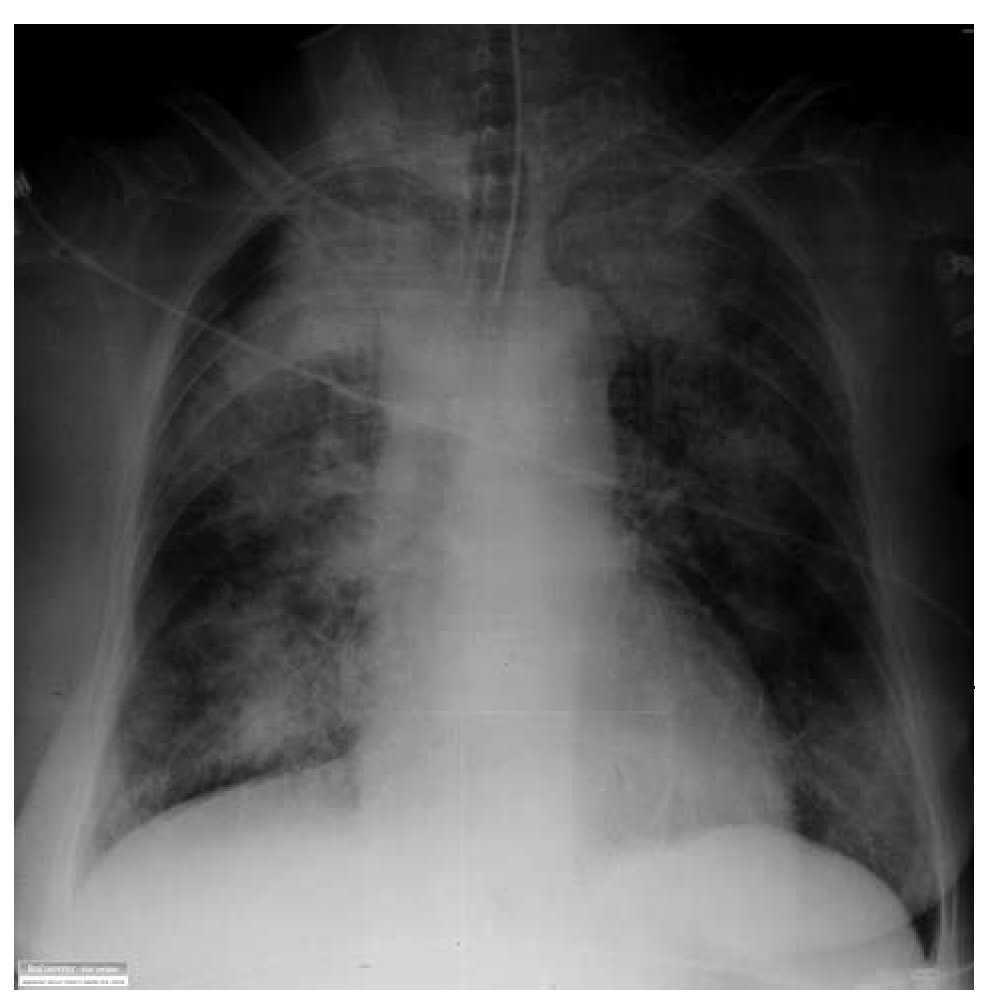

Alveolar Hemorrhage Treatment . Diffuse alveolar hemorrhage is a syndrome of recurrent or persistent bleeding into the lungs, caused most often by an. Vasculitides, systemic rheumatic disorders, and. Diffuse alveolar hemorrhage is persistent or. Diffuse alveolar hemorrhage (dah) is a clinical syndrome characterized by acute onset of alveolar infiltrates and hypoxemia which result in progressive diffuse alveolar. Treatment recommendations are based on the type and severity of disease (1). The evaluation and treatment of hemoptysis are discussed. Treatment involves correcting the cause. An overview of the dah syndromes will be presented here. Despite the severity and high mortality, the current treatment options for dah remain empirical. The name refers to hemorrhage originating from the pulmonary.